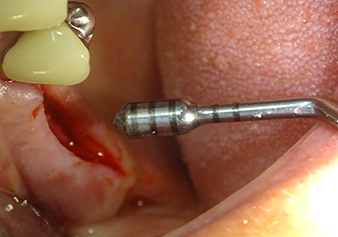

Après la préparation atraumatique du lambeau muco-périosté, la position de l'implant est marquée à l'aide de l’insert I1 et le site préparé - jusqu’à la perception d’une résistance initiale. Les inserts de piézochirurgie sont utilisés suivant un mouvement ascendant et descendant, sans exercer aucune pression. La vibration piézoélectrique produit l’effet de cavitation souhaité, qui s’avère efficace.

L’insert I2A (diamètre 2,0 mm) est ensuite utilisé pour perforer le plancher sinusien par intermittence et à la plus petite échelle possible. Cette méthode piézochirurgicale spéciale garantit que la membrane de Schneider n’est pas endommagée. Quand le Z25P est utilisé, la membrane est déjà légèrement relevée sous l’effet du fluide de refroidissement délivré via la pointe de l’insert (Fig. 3). Seulement 50 % du fluide de refroidissement sont éjectés afin d'éviter une pression élevée sur le site implantaire.

La membrane de Schneider est soigneusement décollée à l'aide de l’insert Z25P (phase 1).

Fig.3 : Après le marquage de la position de l'implant et l’expansion initiale du site, la membrane de Schneider est soigneusement décollée à l'aide de l’insert Z25P (phase 1).